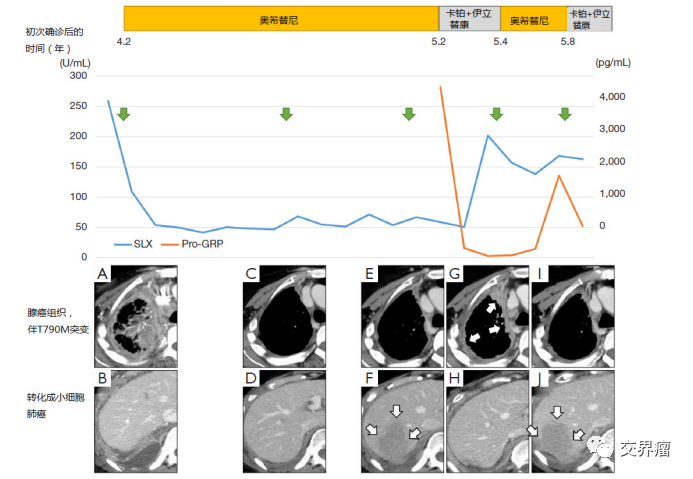

5.耐药也有可能是因为发生小细胞转化

在我们长期用药驱使下,肺癌也有可能发生病理转化,如从肺腺癌或肺鳞癌转化为小细胞肺癌,或部分转化。如何发现呢?有三种方式可以终点参考:①肿瘤标志物中神经元特异性烯醇化酶(NSE)指标异常增高;②基因检测中发现RB1和TP53的突变;③其他病灶对治疗有效,唯一处病灶(可以是新发病灶)出现异常增大,生物学行为与其他病灶细胞不同。这三种情况下需高度怀疑小细胞肺癌转化的情况。当然最终确证仍需病理活检。一旦确定确实存在转化,治疗方法就是要联用小细胞肺癌的化疗方案EP/IP。